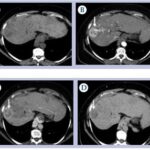

El principal factor de riesgo para su desarrollo es la cirrosis, principalmente la relacionada con la hepatitis viral crónica. Es este caso la hepatitis C, cirrosis alcohólica, cirrosis causada por hemocromatosis y cirrosis biliar primaria. La mayor parte de los casos en esta zona están relacionados con el virus de la hepatitis B, asociado o no con aflatoxina (micotoxinas producidas por dos especies de Aspergillus, un hongo localizado en especial en zonas con climas cálidos y húmedos). En el estudio de tomografía multicorte con técnica multifase el carcinoma hepatocelular (CHC) tiene vascularización predominantemente arterial, lo que determina un patrón de comportamiento específico caracterizado por un intenso reforzamiento en fase arterial, seguida de un lavado (washout) rápido en fase venosa portal, y en muchos casos la presencia de una seudocápsula en fases tardías. Este patrón ha resultado ser específico para el diagnóstico de carcinoma hepatocelular.(17-18)

El CHC presenta una vascularización predominantemente arterial (por neovascularización) a medida que avanza el proceso de hepatocarcinogénesis, a diferencia del parénquima hepático, en donde la vascularización es mixta: arterial y portal. Este patrón característico, favorecido por la alta probabilidad del CHC en pacientes con hepatopatía crónica, ha mostrado una especificidad próxima al 100% para el diagnóstico de CHC. No obstante, este patrón vascular está penalizado por una sensibilidad del 60%-70% en lesiones de pequeño tamaño, y se ha descrito que alrededor de un 15% delos CHC de pequeño tamaño son hipovasculares al no haber desarrollado aún su neovascularización, sin que ello indique que estas lesiones tengan un comportamiento menos agresivo.(18-21) No obstante, en ocasiones el carcinoma hepatocelular puede ser hipovascular y no mostrar reforzamiento intenso en la fase arterial, siendo en estos casos muy importantes las fases venosas portal y venosa tardía, en donde la lesión permanece hipodensa o incluso puede presentar un comportamiento atípico con importante reforzamiento en la fase arterial y ausencia de lavado tardío (Anexos 10 y 11).